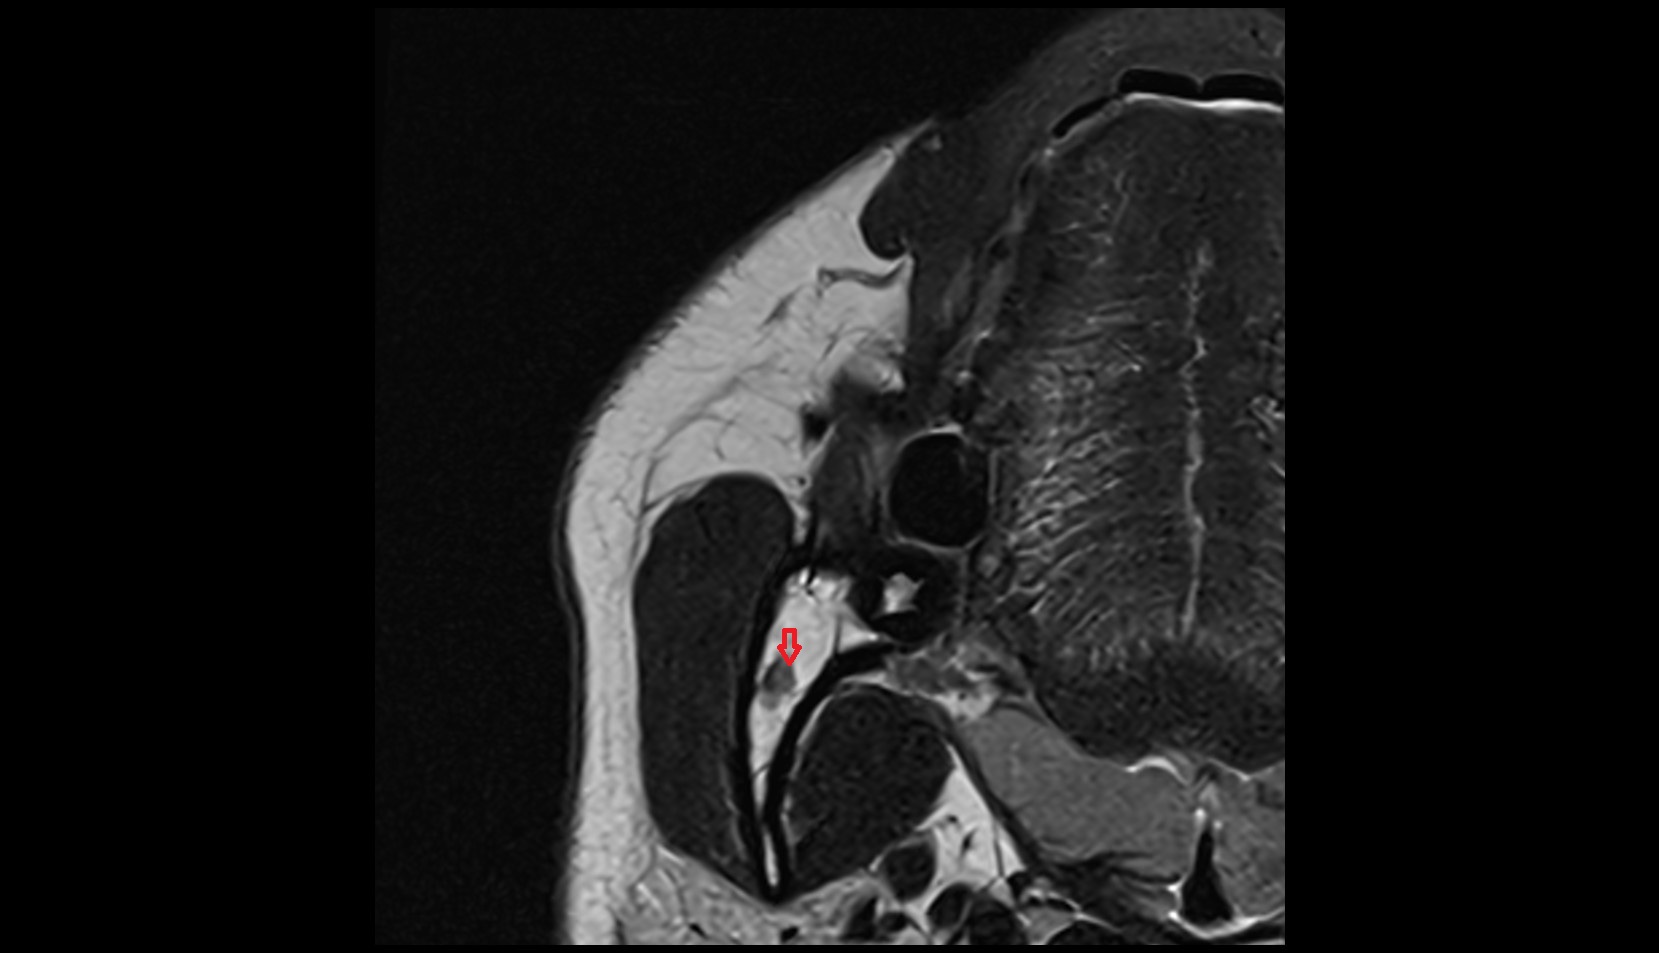

- Hippocampal head